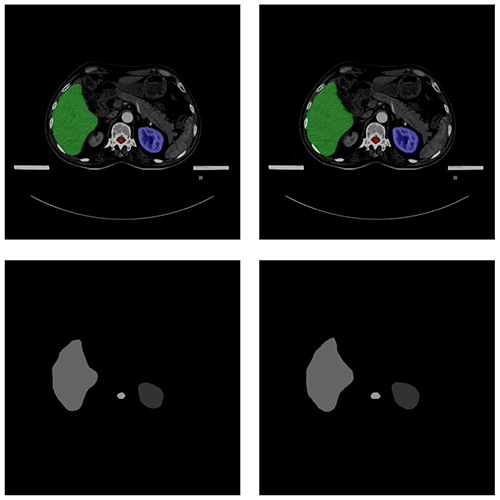

自動勾畫效果

AUTOMATIC CONTOURING

原圖

預測圖